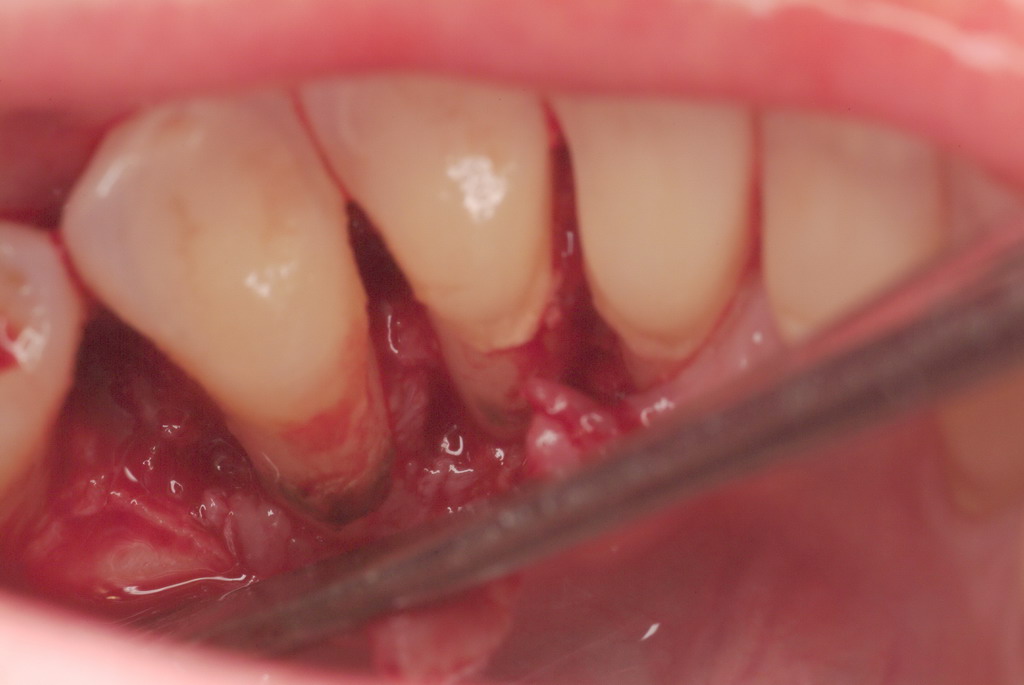

In a case with an intrabony defect, such as with the patient in Figure 17, a periodontist might suggest sacrificing supporting bone to remove the osseous defect. Doing this might lead to issues related to tooth mobility, esthetics, caries, and hypersensitivity.

The patient had been referred for an implant consultation for the mandibular right canine. She had very deep probing depths on the lingual. When the flap was raised, a significant amount of subgingival calculus was seen as a local risk factor (Figure 18). However, she had no significant pathology to remove from the situation. Debridement was performed the same as in Case 3 with the rotary ultrasonic and manual instrumentation.

A significant intrabony defect around tooth No. 27.

Figure 17

Subgingival calculus and severe bone loss.

Figure 18